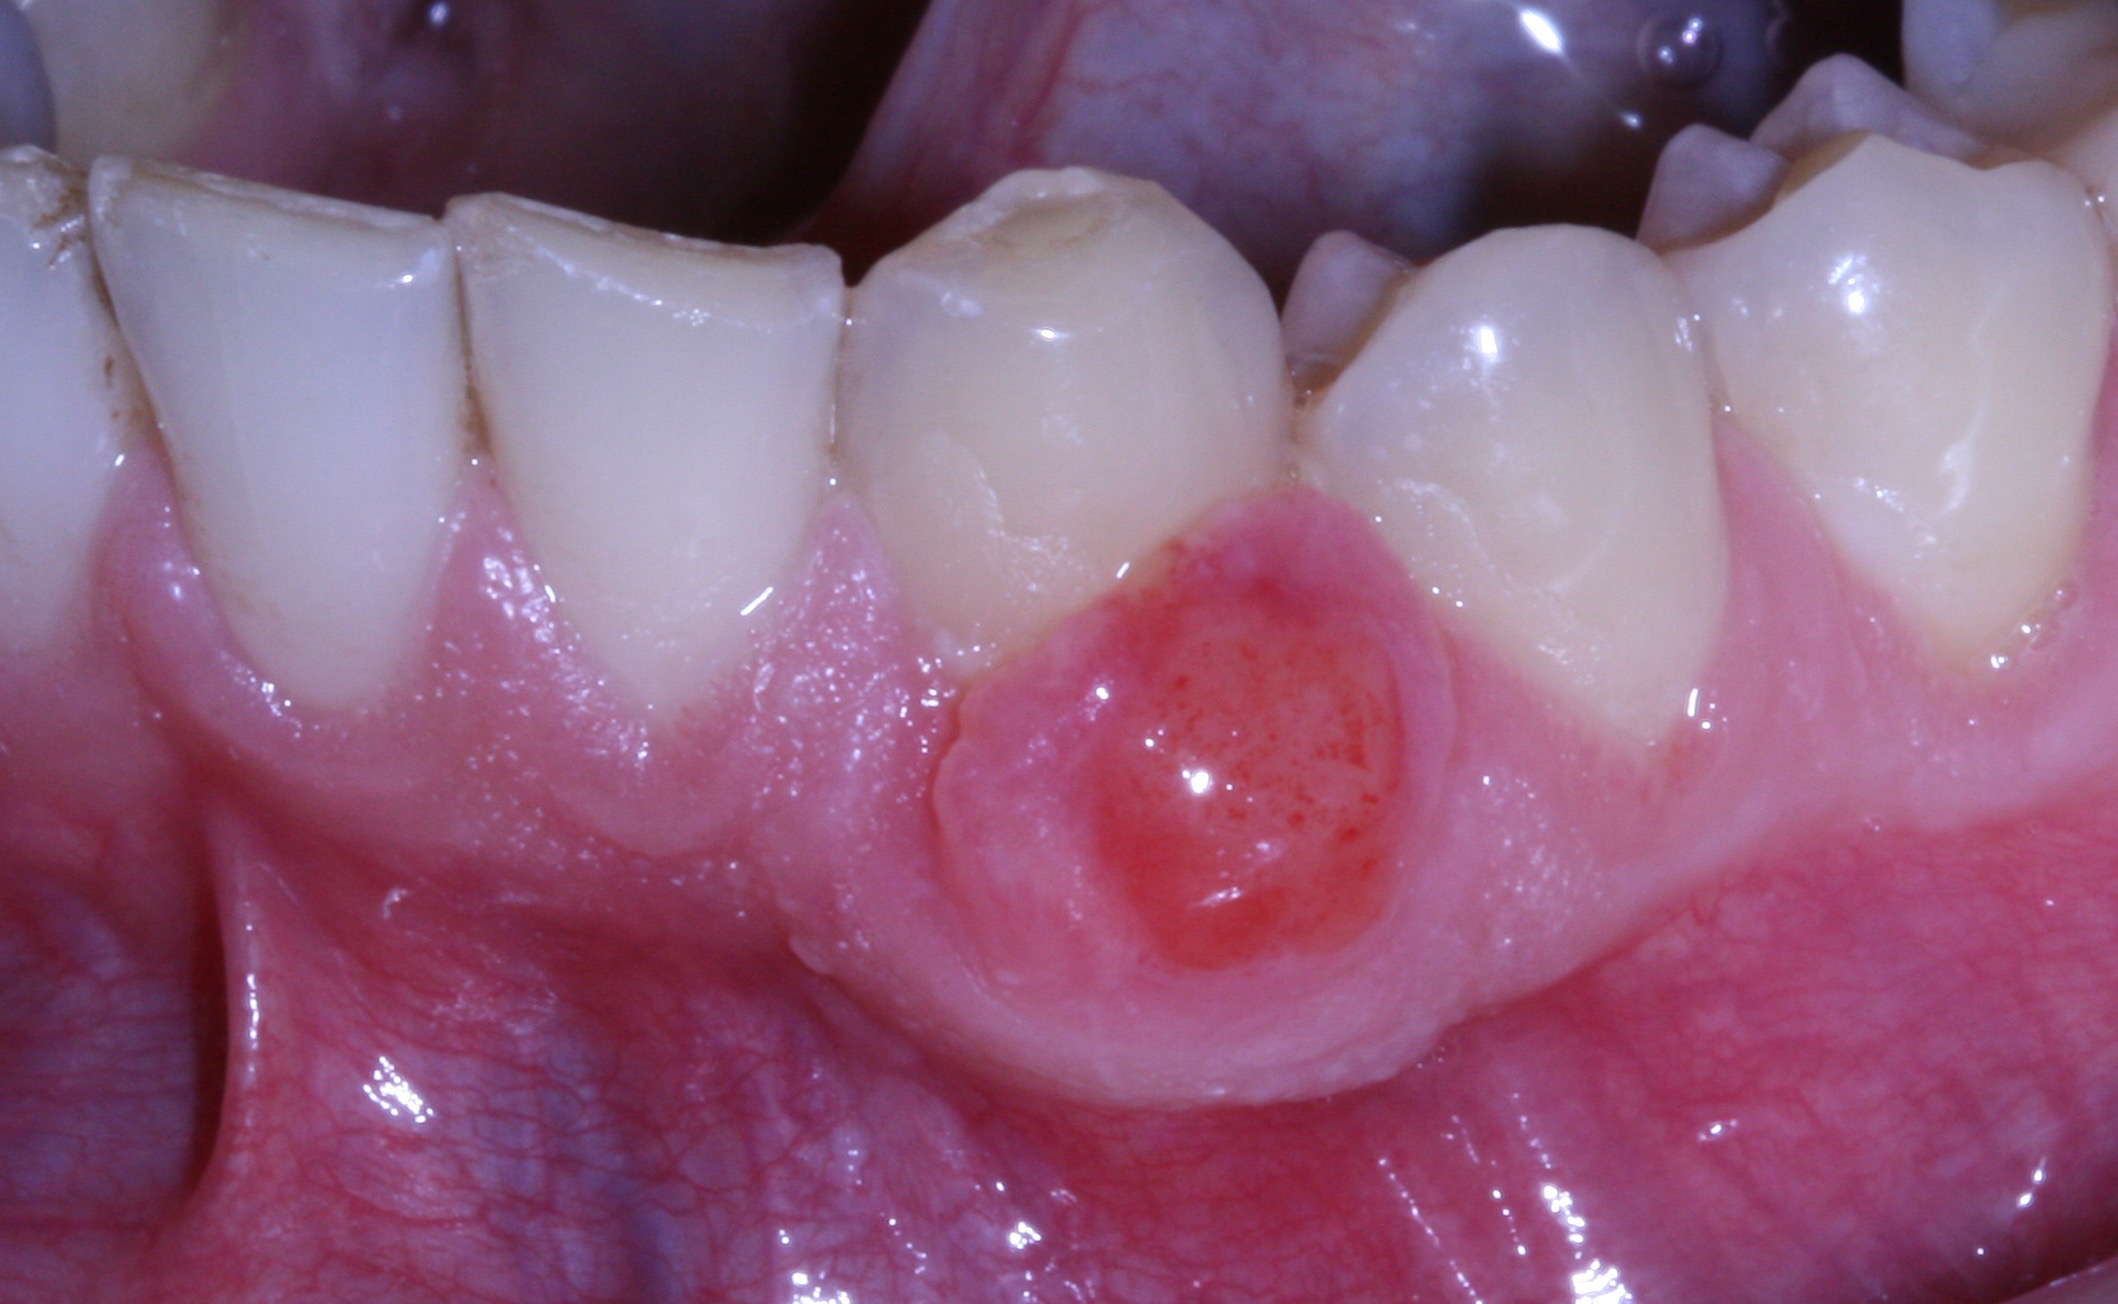

Guarigione della gengiva dopo 7 giorni